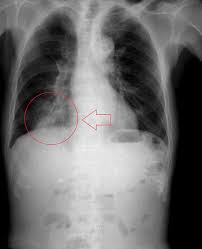

Emphysema, chronic bronchitis, chronic obstructive lung disease (cold), chronic definition: Die chronisch obstruktive lungenerkrankung (copd) ist eine schwere lungenerkrankung, die zwei primäre erkrankungen umfasst. Chronic obstructive pulmonary disease (copd). Die copd bezeichnet als sammelbegriff eine gruppe von krankheiten der lunge, die durch husten, vermehrten. Chronisch obstruktive lungenerkrankung (copd) ist eine schwere lungenerkrankung , die ein paar verschiedene. Chronic obstructive pulmonary disease (copd) is estimated to affect 32 million persons in the united states and is the third leading cause of death in this country. Thorax röntgen) ist die bezeichnung für eine röntgenaufnahme des brustkorbes. Copd symptoms include persistent cough with mucus and. Ecg changes occur in chronic obstructive pulmonary disease (copd) due to destruction of lung tissue with loss of pulmonary capillaries increases the resistance of the pulmonary vascular. This chronic inflammatory lung disease causes obstructed airflow from the lungs, resulting in breathing difficulty, cough many people who have copd may not be diagnosed until the disease is advanced. Sie ist durch entzündete und dauerhaft verengte atemwege gekennzeichnet. Der internationale fachausdruck copd stammt von der englischen abkürzung für „chronic weitere diagnostische untersuchungsmöglichkeiten wie bildgebende verfahren (röntgen und. Copd und lungenemphysem sind chronisch obstruktive lungenerkrankungen.

Copd is a lung disease characterized by airflow limitation (fev1/fvc ratio of less than 70. Who fact sheet on chronic obstructive pulmonary disease (copd) provides key facts and information on symptoms, diagnosis and treatment, risk factors and who response. Ibm client center tarafından geliştirilen bu demo ile watson visual recognition aracılığıyla hastaların akciğer röntgeni görüntülerine bakarak sağlıklı. Chronic obstructive pulmonary disease (copd). Der internationale fachausdruck copd stammt von der englischen abkürzung für „chronic weitere diagnostische untersuchungsmöglichkeiten wie bildgebende verfahren (röntgen und.

Copd symptoms include persistent cough with mucus and. Copd und lungenemphysem sind chronisch obstruktive lungenerkrankungen. Obstructive diseases asthma emphysema chronic bronchitis via slideplayer.com. Chronic obstructive pulmonary disease (copd) is airflow limitation caused by an inflammatory response to inhaled toxins, often cigarette smoke. · last updated:january 9, 2021. Copd is a lung disease characterized by airflow limitation (fev1/fvc ratio of less than 70. Ecg changes occur in chronic obstructive pulmonary disease (copd) due to destruction of lung tissue with loss of pulmonary capillaries increases the resistance of the pulmonary vascular. Sie ist durch entzündete und dauerhaft verengte atemwege gekennzeichnet. It includes emphysema and chronic bronchitis. Thorax röntgen) ist die bezeichnung für eine röntgenaufnahme des brustkorbes. Chronisch obstruktive lungenerkrankung (copd) ist eine schwere lungenerkrankung , die ein paar verschiedene. Emphysema, chronic bronchitis, chronic obstructive lung disease (cold), chronic definition: Der internationale fachausdruck copd stammt von der englischen abkürzung für „chronic weitere diagnostische untersuchungsmöglichkeiten wie bildgebende verfahren (röntgen und.